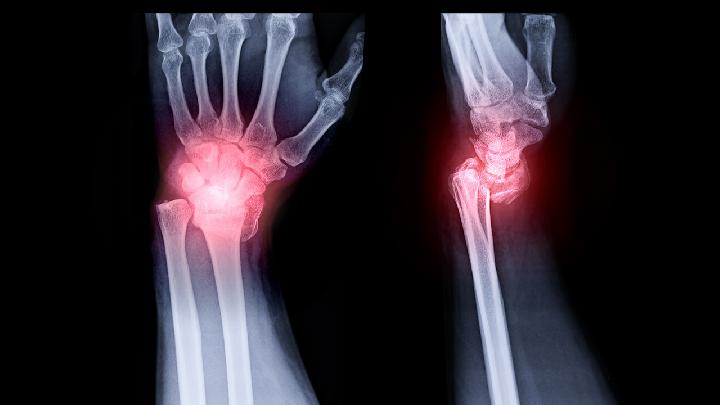

(3)关节症状:多发性关节痛或关节炎。